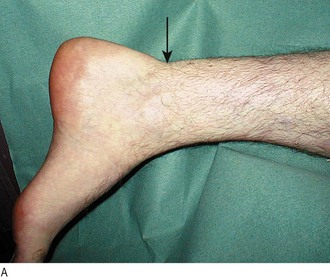

Achilles tendon rupture (see Fig. 14.55) is associated with attempted sudden plantar flexion at the ankle. It is common in middle-aged patients doing unaccustomed activity, e.g. badminton, squash or the fathers’ race at sports day, and is associated with some drug therapy, e.g. oral steroids, fluoroquinolone antibiotics. Sudden pain occurs above the heel and there is often a sensation or noise of a crack. Patients may feel as if they have been kicked or even shot.

Fig. 14.55 Ruptured Achilles tendon. (A) The arrow indicates the site of a palpable defect in the Achilles tendon. (B) Thomson’s test. Failure of the foot to plantar flex when the calf is squeezed is pathognomonic of an acute rupture of the Achilles tendon.